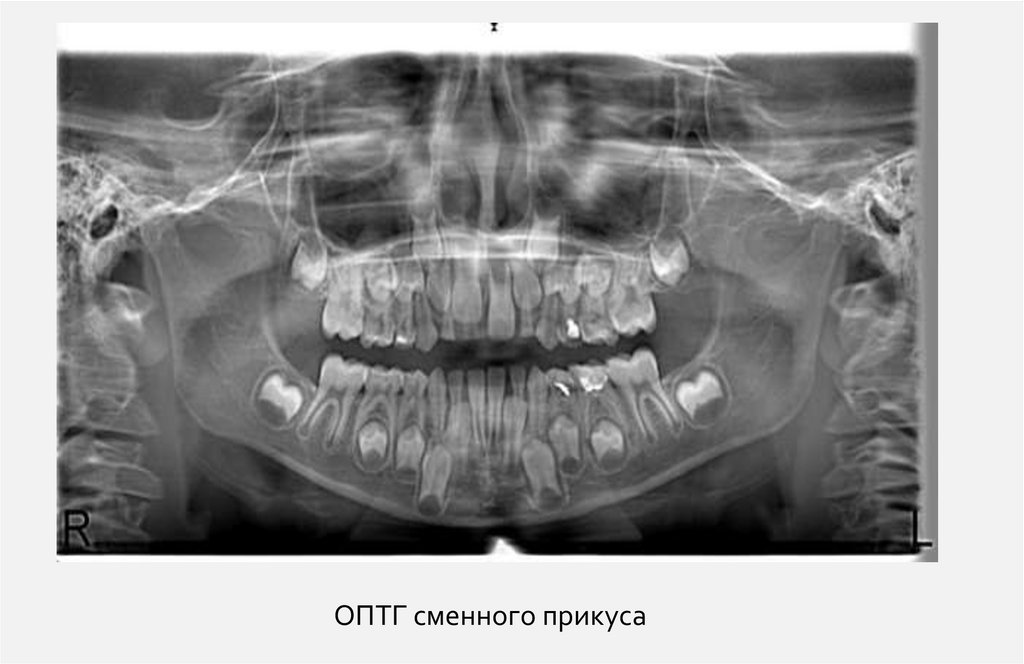

ОПТГ сменного прикуса